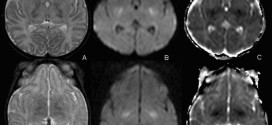

La ataxia telangiectasia, también llamado (Síndrome de Louis-bar). La ataxia telangiectasia (AT) es una enfermedad genética, causada por una mutación en el gen ataxia-telangiectasia mutado (ATm), de transmisión autosómica recesiva, que se localiza en el brazo largo del cromosoma 11. El gen afectado codifica una enzima del tipo fosfatidilinositol quinasa tipo 3 implicada en el control del ciclo celular. Es …